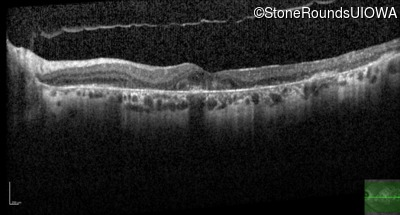

AR Stargardt Disease (IIA)

Age at visit: 59 years

This 59 year old man has noticed some blank spots near the center of his vision over the last 2 years.

Diagnosis & molecular findings

Disease Gene Allele 1 variant(s) Allele 2 variant(s) Inheritance mode

AR Stargardt Disease ABCA4 Leu2027Phe CTC>TTC IVS30+1321 A>G AR